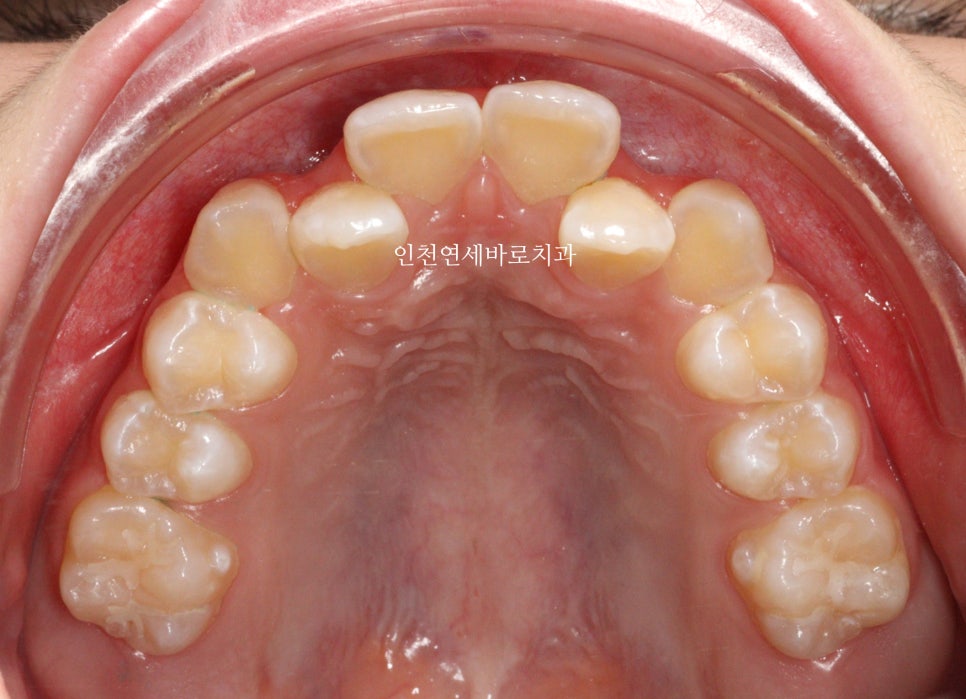

| 주요 증상 | 두번째 치아 덧니 |

두번째 치아가 덧니로 있는 경우의 치료는 흔한 경우지만

생각보다 많은 노하우가 필요한 치료라고 생각합니다.

최후방 치아 맹출에 따른 치료기간 연장

교정 치료 중에 화살표 최후방 치아가 맹출하여,

이 치아를 배열하는 과정에서 치료가 조금 더 길어지긴 했습니다